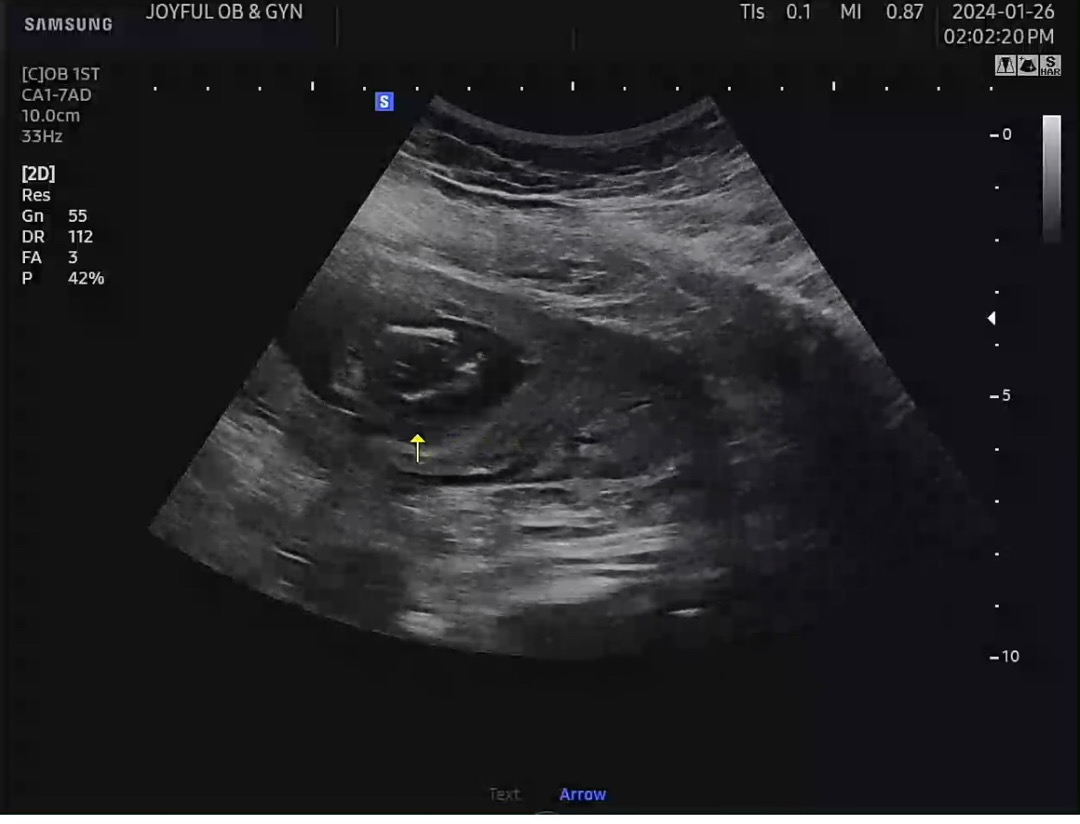

14주차 2일 성별 궁금해요ㅜㅜ

성별이 뭔지 궁금한데ㅜㅜ 초음파로 가늠이될까요?